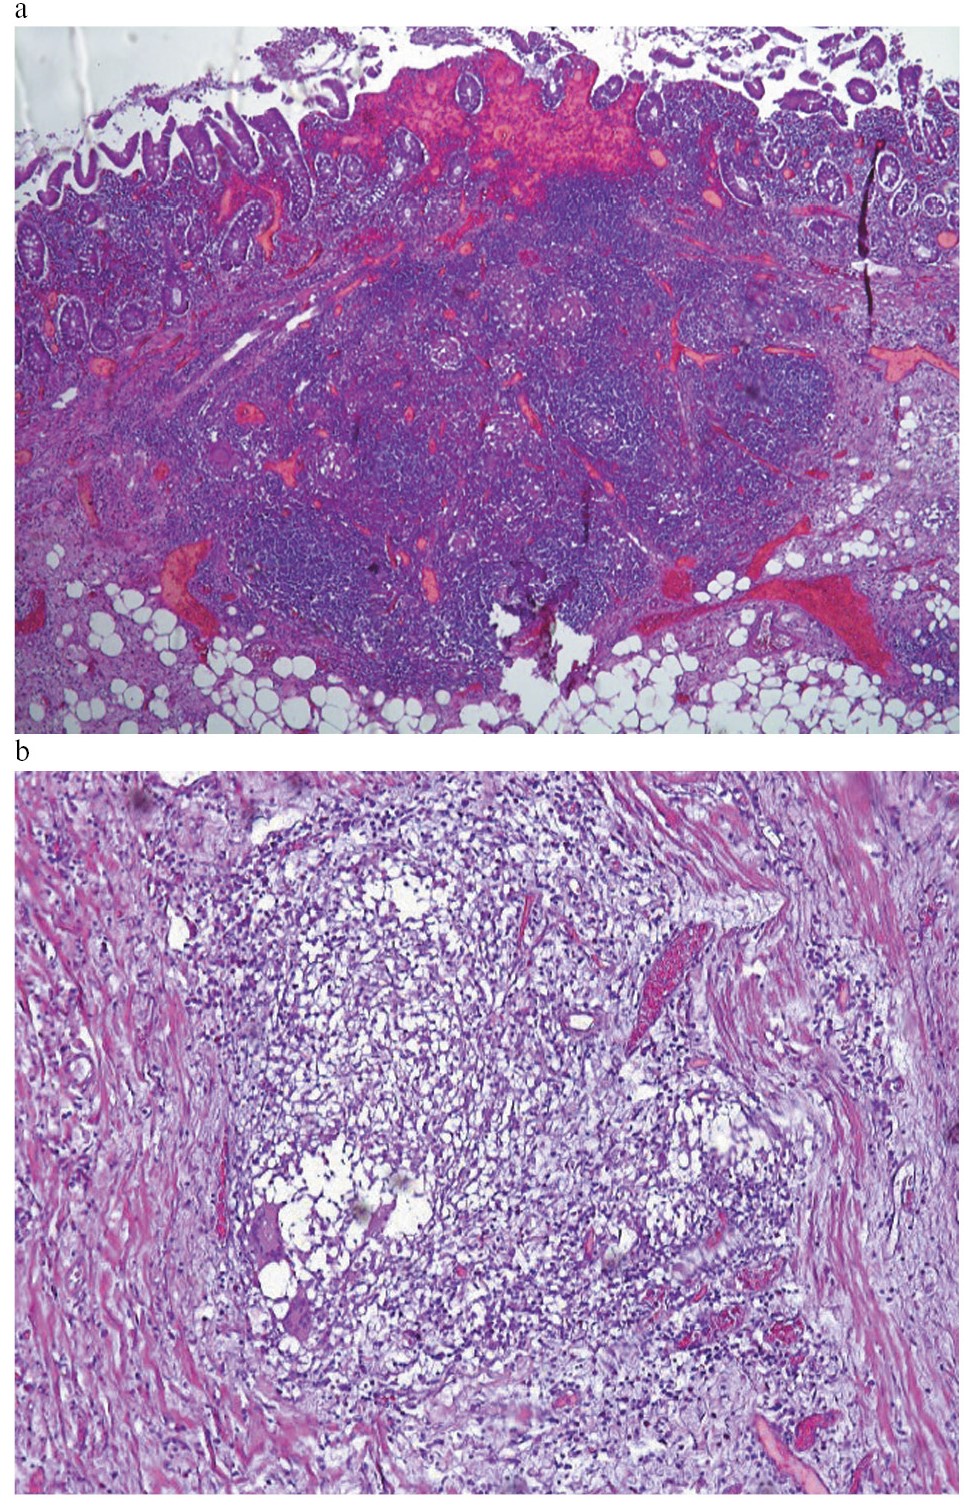

При морфологическом исследовании впервые выявлены признаки БК двенадцатиперстной кишки – ДПК (рис. 2).

Рис. 2. БК с поражением ДПК: a – деструкция кишечных ворсин и крипт с формированием глубокой щелевидной эрозии; b – участки гранулематозного воспаления в собственной пластинке слизистой оболочки ДПК; c – гигантские многоядерные клетки в участках гранулематозного воспаления. Окраска гематоксилином и эозином. Увеличение: a, b – ×120; c – ×500.

Fig. 2. Crohn's disease of the duodenum: a – destruction of intestinal villi and crypts with the formation of deep slit erosion; b – areas of granulomatous inflammation in the proper plate of the mucous membrane of the duodenum; c – giant multinucleated cells in areas of granulomatous inflammation. Stained with hematoxylin and eosin. Magnification: a, b – ×120; c – ×500.